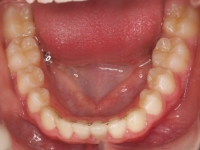

El paciente A.J. de 11 años, acude a nuestra consulta con apiñamiento maxilar importante. El canino lateral (12) está en mordida cruzada. Presenta una Clase II molar y canina, y la línea media está desviada. Se realizó un tratamiento con brackets autoligables metálicos de smartclip 022. La duración del tratamiento fue de 22 meses.

El paciente actualmente ha terminado el tratamiento con brackets y lleva una contención fija de 2-2 en maxilar y 3-3 en mandibular; para complementar también lleva una férula ESSIX durante la noche.

INICIO FINAL